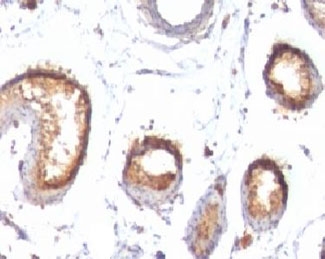

Cytotoxic T lymphocytes (CTL's) recognize melanoma-associated antigens, which belong to three main groups. These groups include tumor-associated testis-specific antigens, melanocyte differentiation antigens and mutated or aberrantly expressed antigens, which are routinely used as markers to identify melanomas based on their binding to specific monoclonal antibodies. gp100, also designated ME20-M, ME20-S and PMEL 17, is classified as a melanocyte differentiation antigen and is expressed at low levels in normal cell lines and tissues, but is upregulated in melanocytes. gp100 is a highly glycosylated protein. It is also the product of proteolytic cleavage, which results in a secreted protein.

The gp100 molecule is a 100kDa glycosylated protein that is cleaved into a small (26kDa) carboxy-terminal fragment and a larger amino- terminal section (60-64 kDa), which is subsequently cleaved to generate 26kDa and 34-38kDa fragments.